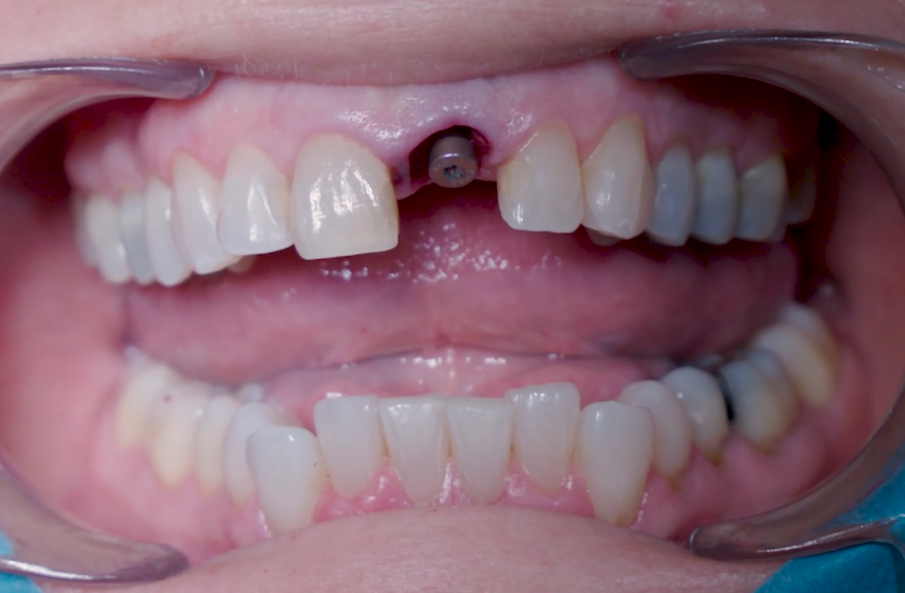

Una paziente di 53 anni si è presentata in studio con un incisivo sinistro fratturato a cui era stata più volte cementata una corona di ceramica (Figg. 1, 2). L’anamnesi e gli esami hanno evidenziato una buona salute sistemica e orale, un’occlusione ben equilibrata e nessuna abitudine al fumo. La tomografia cone beam (CBCT) e la radiografia periapicale hanno mostrato un riassorbimento radicolare esterno con inserimento nell’osso alveolare molto scarso, insufficiente per un adeguato posizionamento di un comune perno endocanalare (Figg. 3, 4). Considerando che il dente fratturato si trovava nella zona estetica, il paziente richiese un restauro nel modo più sicuro e più veloce possibile.

Fig. 1_Situazione iniziale, visione extra-orale.

Fig. 2_Situazione iniziale, visione intra-orale.

Fig. 28_Corona temporanea una settimana dopo l'operazione.